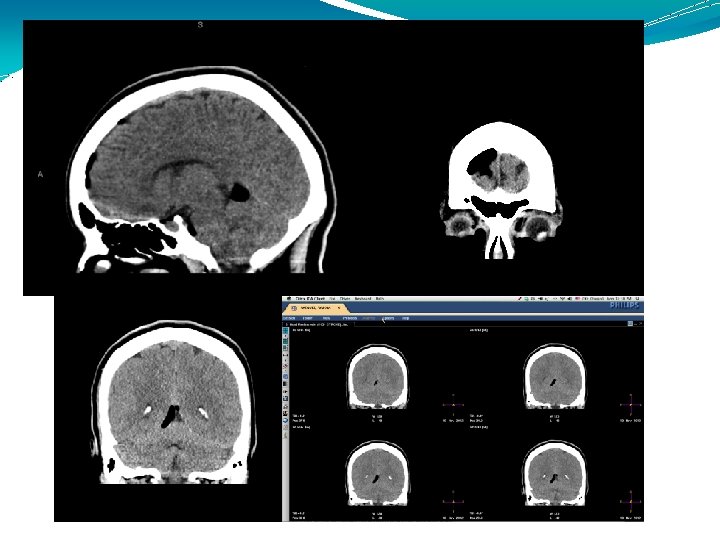

机制 CSF渗漏 直立时颅内结构有一个向下的牵引力 CSF容量下降 通过血管舒张,使脑部血流量代偿性增加 Monro-Kellie doctrine Alexander Monro, Scottish anatomist and surgeon, 1733

机制 CSF渗漏 直立时颅内结构有一个向下的牵引力 CSF容量下降 通过血管舒张,使脑部血流量代偿性增加 Monro-Kellie doctrine Alexander Monro, Scottish anatomist and surgeon, 1733 -1817; George Kellie, Scottish anatomist, late 18 th century: An increase in volume of one component in the CNS will elevate pressure and decrease the volume of one of the other elements. Mosby's Medical Dictionary, 2009